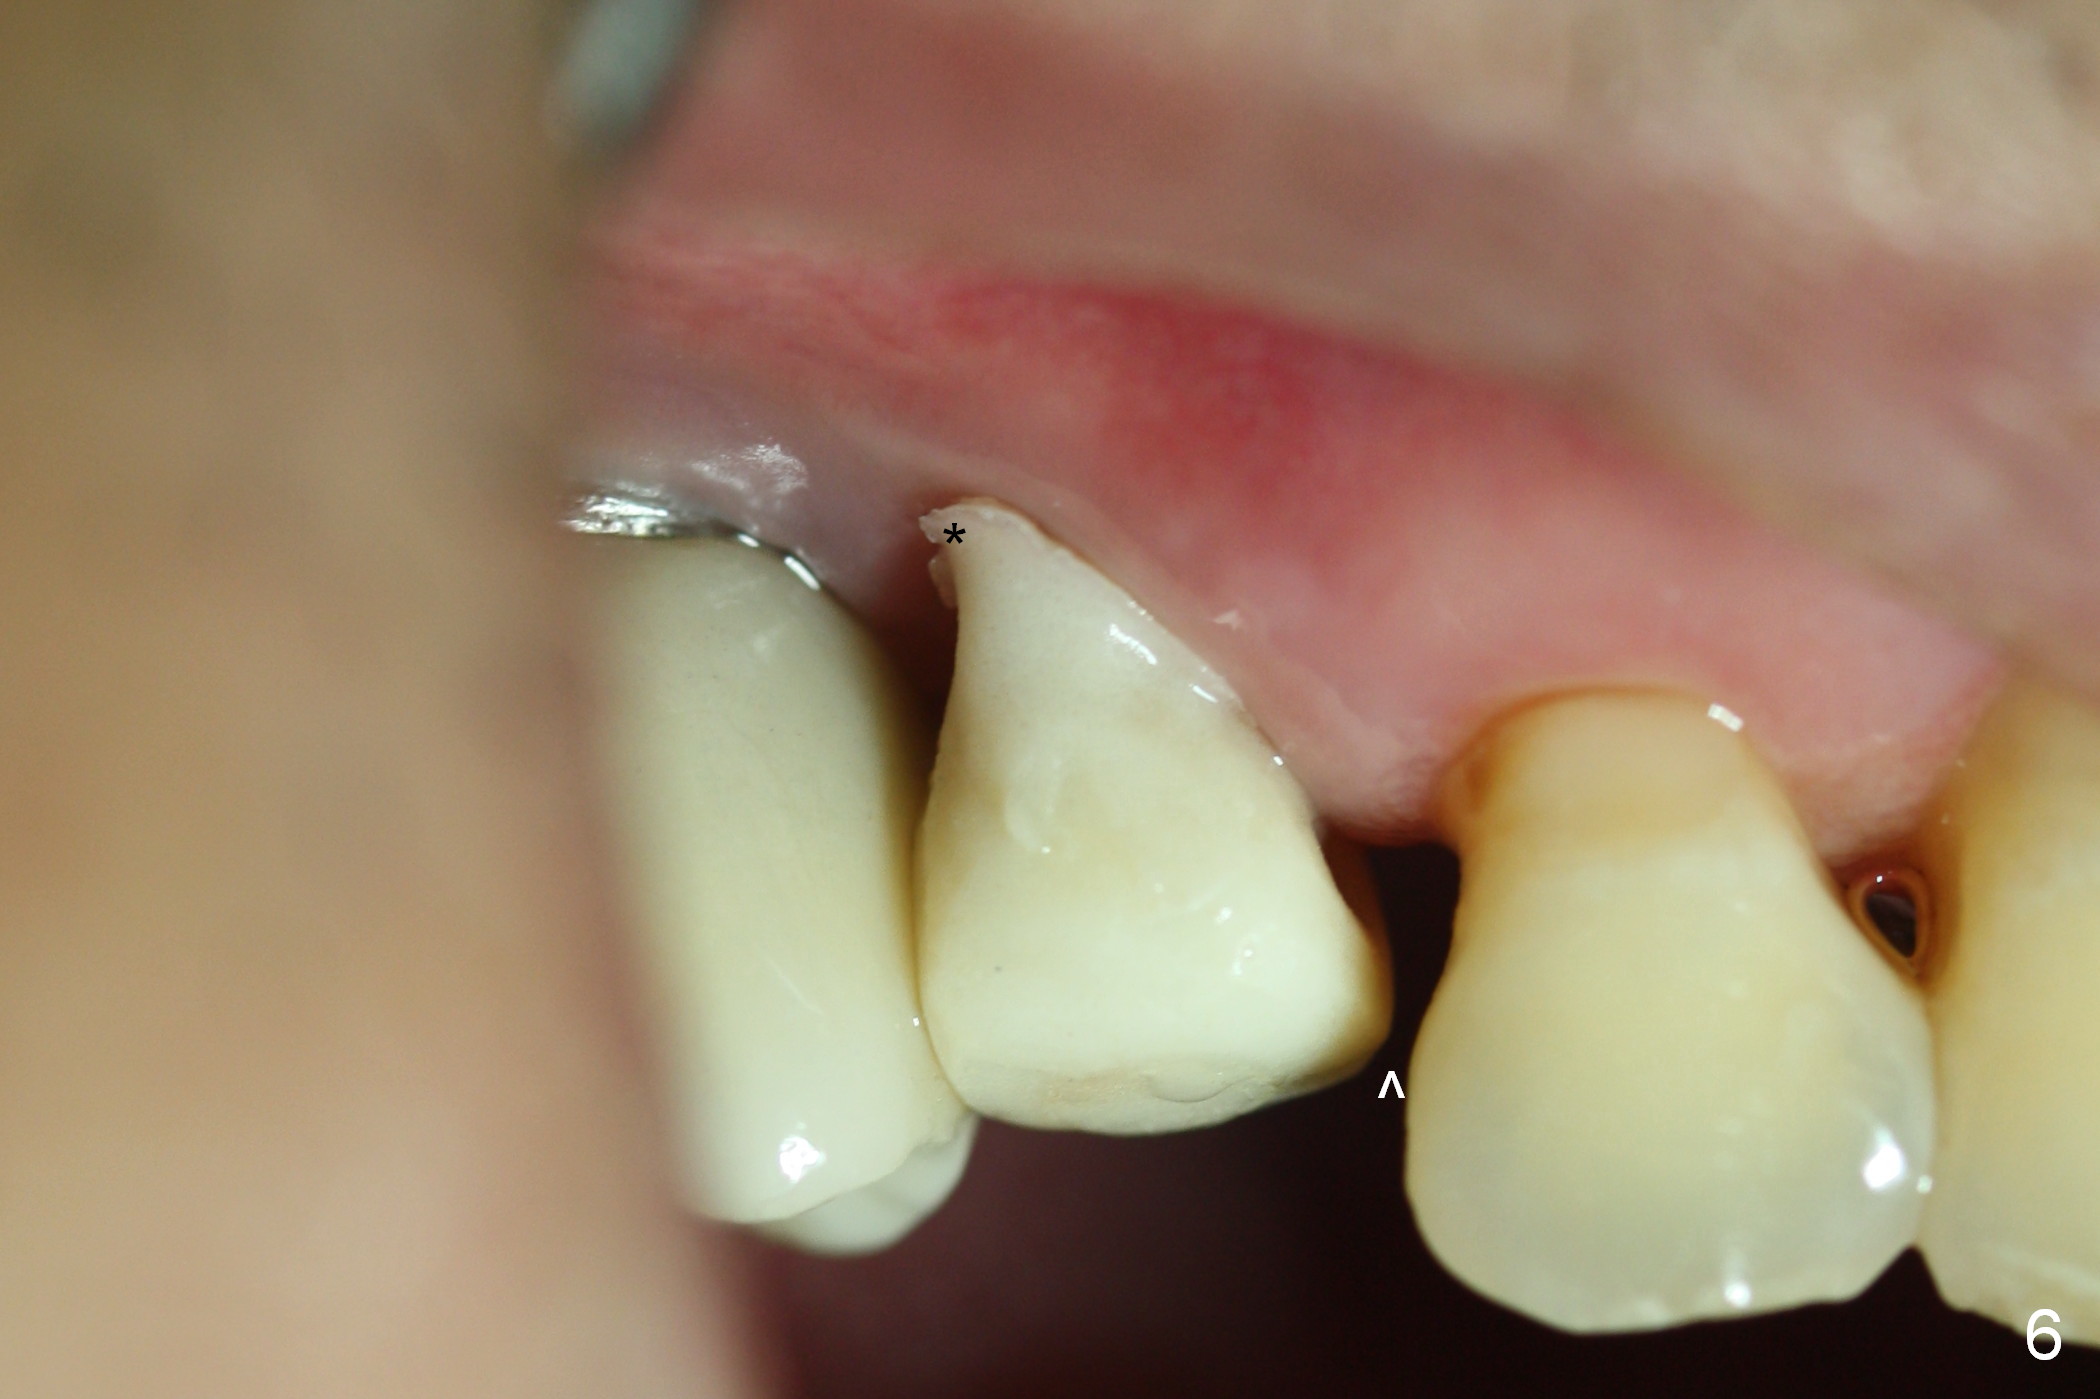

Six days postop, the distobuccal margin of the immediate provisional appears to be overbuilt (Fig.6 *). The overhang was made to cover the distobuccal opening of the socket (Fig.4). In addition to daily use of water pik, cleaning with .25% Sodium Hypochlorite contributes to the shiny surface of the provisional. From now on, use cotton pellets soaked with the diluted bleach to clean the provisional and abutment (if exposed) every visit. For this case, the overhang will be trimmed when the patient returns in 2 weeks so that the distal papilla may grow downward. The mesial contact should be re-established (^).